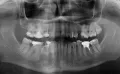

Пациенту поставили мосты и коронки. Все сделано качественно, но теперь пациент утверждает, что испытывает дискомфорт от коронок на нижней челюсти, и требует вернуть ему все деньги и всю ранее выполненную работу (коронки и мосты).